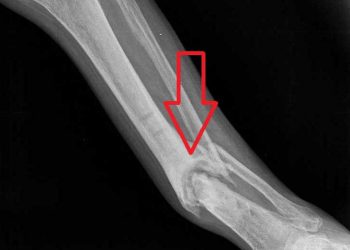

Yalancı Eklem, kırıkta hareketsizliğin sağlanamaması nedeniyle kırık uçlarının fibrokartilaj yapıda sert bir tabakayla örtülmesi ve kaynamanın olmayıp kırık uçlarının sanki...